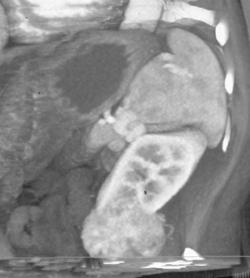

Failed Right Iliac Fossa Renal Transplant That Is Calcified